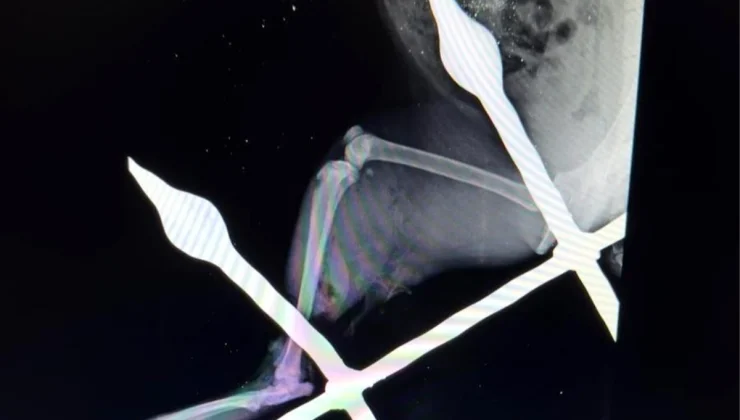

Yaralı kedinin bacağını eski sağlığına kavuşturduklarını anlatan Mersin Büyükşehir Belediyesi Tarımsal Hizmetler Dairesinde Veteriner Hekim olarak görev yapan Yusuf İncir, “Yapılan ilk tespitler sonucunda, balkon demirinin bacağından yaklaşık 10-15 santimetre civarında geçtiği görülmüştür. Yapılan dezenfeksiyon ve temizlik işlemlerinin ardından, balkon demiri anestezi altındaki kedinin bacağından çıkarıldı. Çıkarılırken dokuya mümkün olduğu kadar zarar vermemeye dikkat ettik. Yaptığımız tespitlerde kaslardan bir tanesinin kopmuş olduğu, yalnız sinir dokusunda herhangi bir hasar oluşmadığı tespit edilmiştir. Yapılan yara temizliği ve dezenfeksiyonun ardından, kopan kas kısmı dikişle tekrar eski haline getirildi. Dezenfeksiyonun ardından, yırtılan ve hasar gören dokuların dikiş işlemini gerçekleştirdikten sonra, deri dikişi ile işlemimizi tamamladık. 12 gün zarfında kedimiz sağlığına kavuştu” ifadelerine yer verdi.